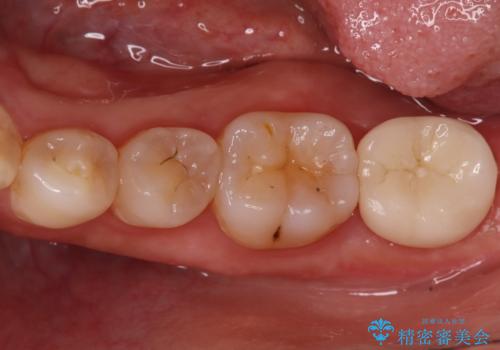

銀歯からセラミックへ。右上奥歯の精密根管治療と審美修復

担当医 河口智英